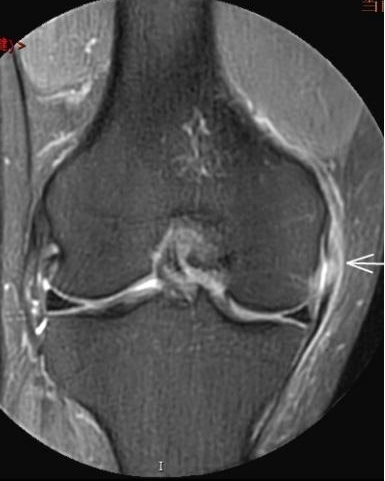

2. 運(yùn)動(dòng)后“打軟腿”——韌帶的“斷弦危機(jī)”

場(chǎng)景:打球急停后膝蓋不穩(wěn),走路像“踩棉花”

MRI偵查:揪出前交叉韌帶斷裂(呈“波浪狀”或連續(xù)性中斷)、內(nèi)側(cè)副韌帶損傷,防止關(guān)節(jié)“脫軌”

(內(nèi)側(cè)副韌帶損傷)